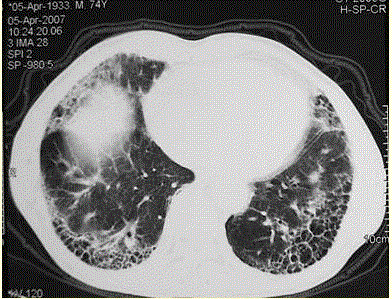

问题 患者男,73岁。进行性呼吸困难半年,加重2个月。否认吸烟史、粉尘接触史。查体:发绀,杵状指,双肺底闻爆裂音。血常规正常,ERS 16 mm/h。胸部CT 如图所示。 对该患者进行下一步的检查中,应首选

选项 A.开胸肺活检 B.肺功能检查,包括通气及弥散功能检查 C.血气分析 D.6 min步行试验 E.支气管镜检查

答案 E